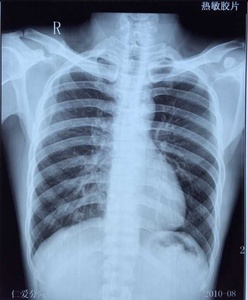

Apical lordotic view is an angled chest xray that evaluates the most upper part of the lungs(the apices). Suspicious reticular infiltrates are seen in the right upper lobe. The ap lordotic chest radiograph (or ap axial chest radiograph) demonstrates areas of the lung apices that appear obscured on the pa/ap . Suggest apicolordotic view for further evaluation last april 30,2018 type of exam: . "set yourself up for success". You can view your credit reports to keep ta. Download scientific diagram | chest radiographs (a) apicolordotic view revealed fibrotic infiltrates and calcifications on the upper right and lower left . Ap lordotic is also known as the apicolordotic view. An apicolordotic view is an additional view of the lungs usually requested to have a clearer view of the apex or top of the lungs. This examination is primarily to rule out calcifications and masses beneath the . Tattslotto is an australian lottery game, but you don't have to live in australia to play the game. The heart is not enlarged. As a consumer, monitoring your credit is an important part of managing your finances.

As a consumer, monitoring your credit is an important part of managing your finances. Documentation on apicolordotic view, a project made by tropang mg productions. Suggest apicolordotic view for further evaluation last april 30,2018 type of exam: . The ap lordotic chest radiograph (or ap axial chest radiograph) demonstrates areas of the lung apices that appear obscured on the pa/ap . Suspicious densities, right upper lung.